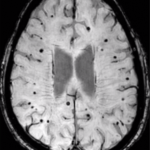

Las microhemorragias (MCHs) cerebrales son una patología vascular frecuente en los pacientes con afecciones vasculares y reconocidas como expresión de la enfermedad de pequeños vasos del cerebro. Su ubicación tiende a determina su causa, aquellas ubicadas en la profundidad del encéfalo, en el centro-encéfalo vascular, se encuentran relacionadas con la microangiopatía cerebral hipertensiva, en tanto aquellas ubicadas en las regiones corticales, son el resultado de la angiopatía amiloide cerebral (AAC).

Las MCHs son visualizadas en las secuencias de eco-gradiente de la resonancia magnética (RM). De acuerdo a los resultados del estudio Rotterdam [1], su prevalencia aumenta con la edad (desde 5% en la edad media hasta el 35% en etapas avanzadas de la vida), pero también suelen observarse en en alta prevalencia en pacientes que sufren el primer episodio de un ataque vasculo-encefálico (ACV) ya sea isquémico o hemorrágico y más aún, con su recurrencia, en pacientes con deterioro cognitivo y en la enfermedad de Alzheimer. Las MCHs han sido asociadas con riesgo incrementado de ACV tanto hemorrágico como isquémico. Es así que, las MCHs comienzan a ser consideradas como un posible “biomarcador de riesgo de sangrado” (hemorragia intracerebral) en pacientes asintomáticos, con ACV previo, con ataques isquémicos transitorios (AIT) o en presencia de fibrilación auricular (FA).